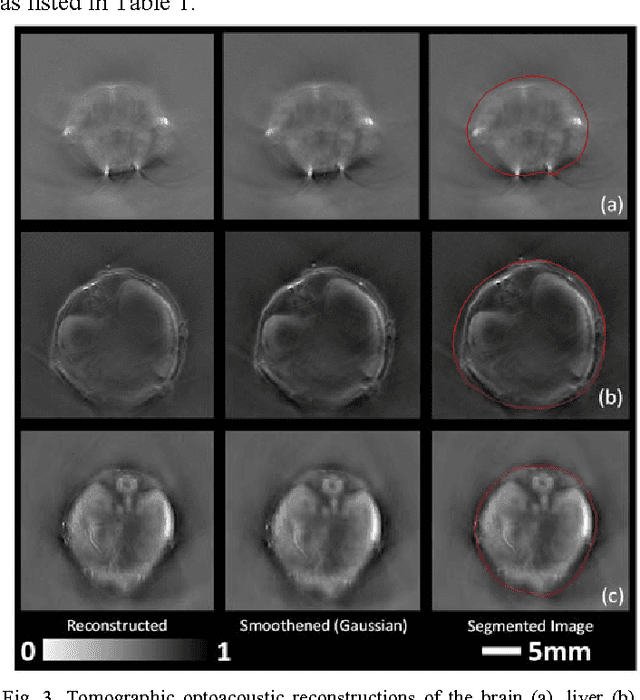

Abstract:Segmentation of biomedical images is essential for studying and characterizing anatomical structures, detection and evaluation of pathological tissues. Segmentation has been further shown to enhance the reconstruction performance in many tomographic imaging modalities by accounting for heterogeneities of the excitation field and tissue properties in the imaged region. This is particularly relevant in optoacoustic tomography, where discontinuities in the optical and acoustic tissue properties, if not properly accounted for, may result in deterioration of the imaging performance. Efficient segmentation of optoacoustic images is often hampered by the relatively low intrinsic contrast of large anatomical structures, which is further impaired by the limited angular coverage of some commonly employed tomographic imaging configurations. Herein, we analyze the performance of active contour models for boundary segmentation in cross-sectional optoacoustic tomography. The segmented mask is employed to construct a two compartment model for the acoustic and optical parameters of the imaged tissues, which is subsequently used to improve accuracy of the image reconstruction routines. The performance of the suggested segmentation and modeling approach are showcased in tissue-mimicking phantoms and small animal imaging experiments.

Abstract:In this article, we present a novel scheme for segmenting the image boundary (with the background) in optoacoustic small animal in vivo imaging systems. The method utilizes a multiscale edge detection algorithm to generate a binary edge map. A scale dependent morphological operation is employed to clean spurious edges. Thereafter, an ellipse is fitted to the edge map through constrained parametric transformations and iterative goodness of fit calculations. The method delimits the tissue edges through the curve fitting model, which has shown high levels of accuracy. Thus, this method enables segmentation of optoacoutic images with minimal human intervention, by eliminating need of scale selection for multiscale processing and seed point determination for contour mapping.